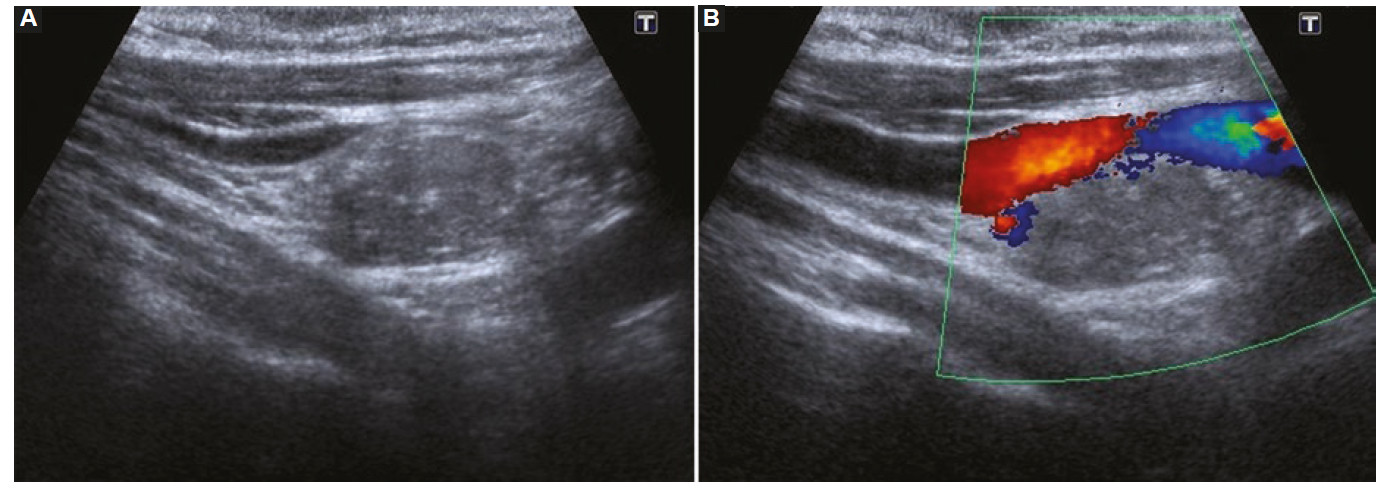

Vascularización

La vascularización se evalúa con la herramienta de Doppler color, y se debe determinar si esta se encuentra ausente (Fig. 18) o aumentada en el nódulo en relación con el parénquima tiroideo. La vascularización aumentada puede presentar dos patrones: central (Fig. 19) y periférico (Fig. 20), siendo el aumento de la vascularización central con disposición caótica la que presenta mayor riesgo de malignidad2,14,19,22,23,24. Un patrón vascular periférico se asocia mayormente con benignidad15,18, aunque algunos autores han calificado a la vascularización como una característica no significativa para diferenciar nódulos benignos de malignos2,3,14,16.